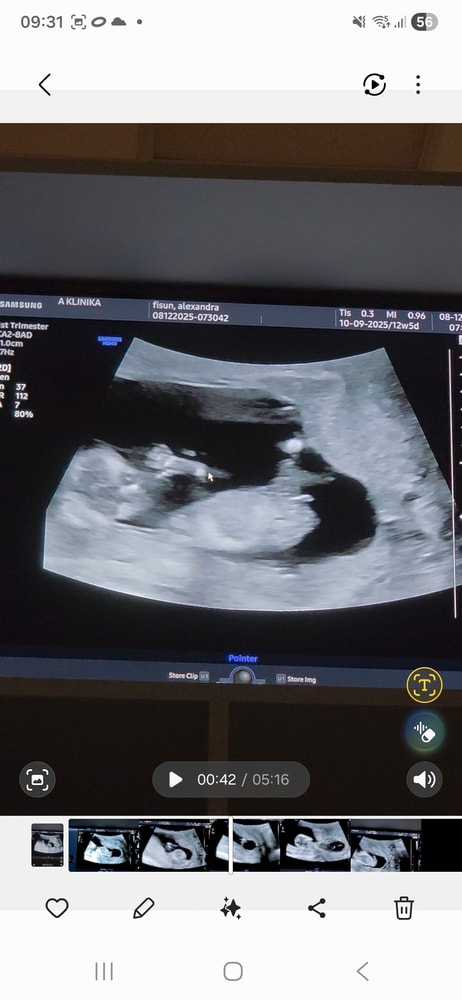

Мальчик или девочка УЗИ 12 недель

Половой бугорок смотрит вниз - девочка)

Ами, ну вот она и у мальчиков и у девочек торчит на таком сроке, только как бы по-разному))

Александра Тарталетка, половой бугорок лежит горизонтально, девочка . Я тоже скриншоты делала , у меня мальчик) Изображение

Больше на мальчика конечно похоже ))))но точнее скажут позже )

Александра , сказали ножки скрещивает, не посмотреть) а это я скриншоты из видео сделала, потому что прям чтобы посмотреть не сбоку, а между ног действительно не получилось, только сбоку кадры)

Александра Тарталетка, по УЗИ можно предположить мальчика но это так же могут быть и половые губы как я читала они у девочек набухшие изначально поэтому по узи точно тут не скажешь )